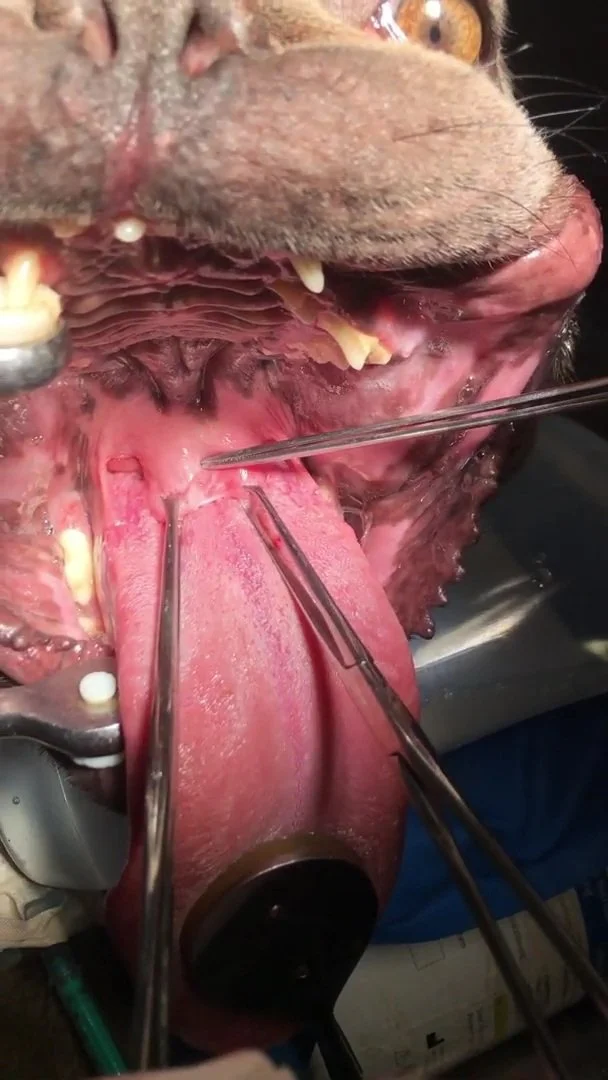

Gaumensegelkürzung

Gaumensegel Operation